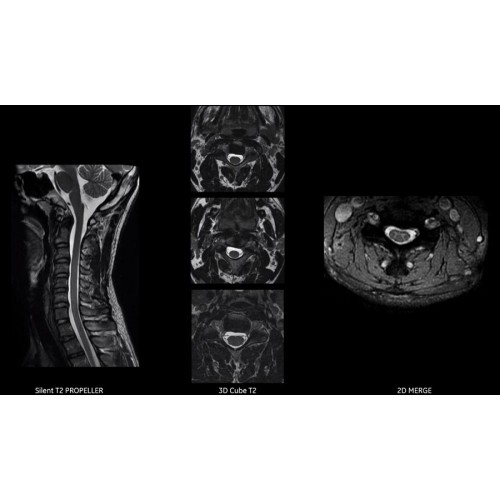

Система SIGNA Pioneer воплощает поразительные достижения в области визуализации. Передовая технология Total Digital Imaging (TDI) позволяет добиться большей четкости изображений и на четверть повысить соотношение сигнал/шум.

• Технология Direct Digital Interface (DDI) использует независимый аналого-цифровой преобразователь для оцифровки сигнала от каждого из 97 радиочастотных каналов, что обеспечивает значительное увеличение качества за счет уменьшения фонового шума.

• Технология Digital Micro Switching (DMS) — это следующее поколение технологий радиочастотных катушек, основанное на замене аналоговых схем блокировки сверхбыстрыми микропереключателями (MEMS), что делает возможным быстрое переключение катушек для дальнейшего расширения возможностей визуализации с нулевым TE.

Благодаря революционному программному пакету Silent Suite уровень шума снижается до 77 дБ, что всего на 3 дБ выше уровня окружающей среды. Программный пакет Silent Suite теперь включает полный пакет приложений для исследования ЦНС (T1, T2 FLAIR, DWI10, МРА). Кроме того, мы расширили возможности визуализации Silent за пределы ЦНС для исследований скелетно-мышечной системы и позвоночника. Silent Suite – платформа, содержащая в себе все импульсные последовательности для бесшумного сканирования.